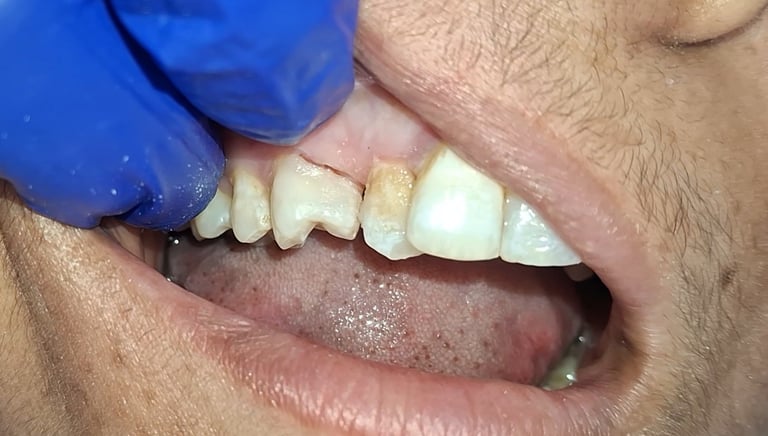

Before

After

All images shown here are real tooth colored filling cases treated at our clinic with patient consent.

At Shree Dental Care, cosmetic fillings are placed carefully with a focus on comfort, precision and long-term durability. We ensure minimal tooth cutting and natural-looking results.

If you are looking for aesthetic tooth colored filling in Shyamal, Ahmedabad, you can book an appointment with our clinic.